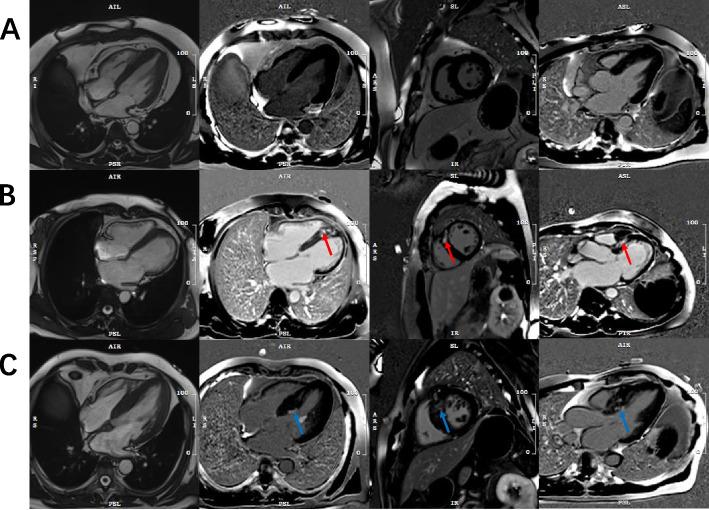

The patients with HCM whom was underwent CMR were enrolled, using cine cardiac magnetic resonance to evaluate LV function and LGE to detect the myocardial fibrosis. Three groups were assorted: 1) HCM without LGE; 2) HCM with LGE involved the subendocardial layer was defined as I-LGE; 3) HCM with LGE not involved the subendocardial layer was defined as NI-LGE.

We enrolled 122 patients with HCM in the present study. LGE was detected in 58 of 122 (48%) patients with HCM, and 22 (18%) of patients reported I-LGE. HCM with I-LGE had increased higher left ventricular mass index (LVMI) (P < 0.0001) than HCM with NI-LGE or without LGE. In addition, HCM with I-LGE had a larger LV end- systolic volume (P = 0.045), lower LV ejection fraction (LVEF) (P = 0.026), higher LV myocardial mass (P < 0.001) and thicker LV wall (P < 0.001) more than HCM without LGE alone. The I-LGE were significantly associated with LVEF (OR: 0.961; P = 0.016), LV mass (OR: 1.028; P < 0.001), and maximal end-diastolic LVWT (OR: 1.567; P < 0.001). On multivariate analysis, LVEF (OR: 0.948; P = 0.013) and maximal end-diastolic LVWT (OR: 1.548; P = 0.001) were associated with higher risk for I-LGE compared to HCM without LGE. Noticeably, the maximal end-diastolic LVWT (OR: 1.316; P = 0.011) was the only associated with NI-LGE compared to HCM without LGE.

I-LGE is not uncommon in patients with HCM. HCM with I-LGE was associated with significant LV hypertrophy, extensive LGE and poor LV ejection fraction. We should consider focal ischemic myocardial fibrosis when applying LGE to risk stratification for HCM.